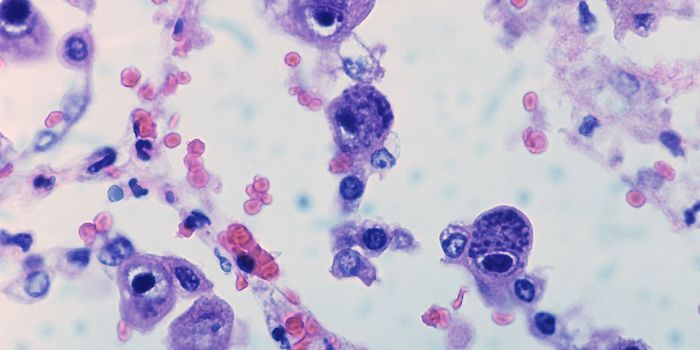

OCT 19, 2023CancerA Pap smear, also called a Pap test or a Papanicolaou test, describes a procedure that removes cells from the surface of ...